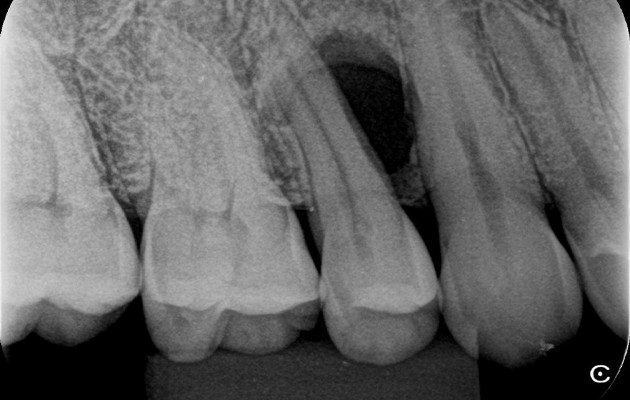

1 | Radiografia periapical inicial revelando uma lesão cística interradicular